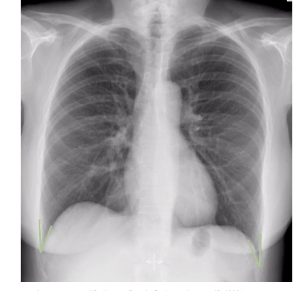

what is this?

costophrenic angle

what is this ?

cardio-phrenic angle